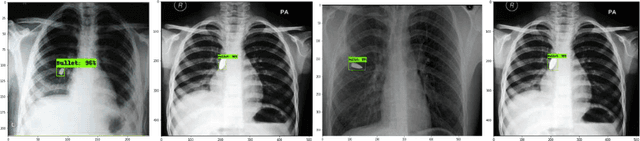

Abstract:The potential of deep learning, especially in medical imaging, initiated astonishing results and improved the methodologies after every passing day. Deep learning in radiology provides the opportunity to classify, detect and segment different diseases automatically. In the proposed study, we worked on a non-trivial aspect of medical imaging where we classified and localized the X-Rays affected by bullets. We tested Images on different classification and localization models to get considerable accuracy. The replicated data set used in the study was replicated on different images of chest X-Rays. The proposed model worked not only on chest radiographs but other body organs X-rays like leg, abdomen, head, even the training dataset based on chest radiographs. Custom models have been used for classification and localization purposes after tuning parameters. Finally, the results of our findings manifested using different frameworks. This might assist the research enlightening towards this field. To the best of our knowledge, this is the first study on the detection and classification of radiographs affected by bullets using deep learning.